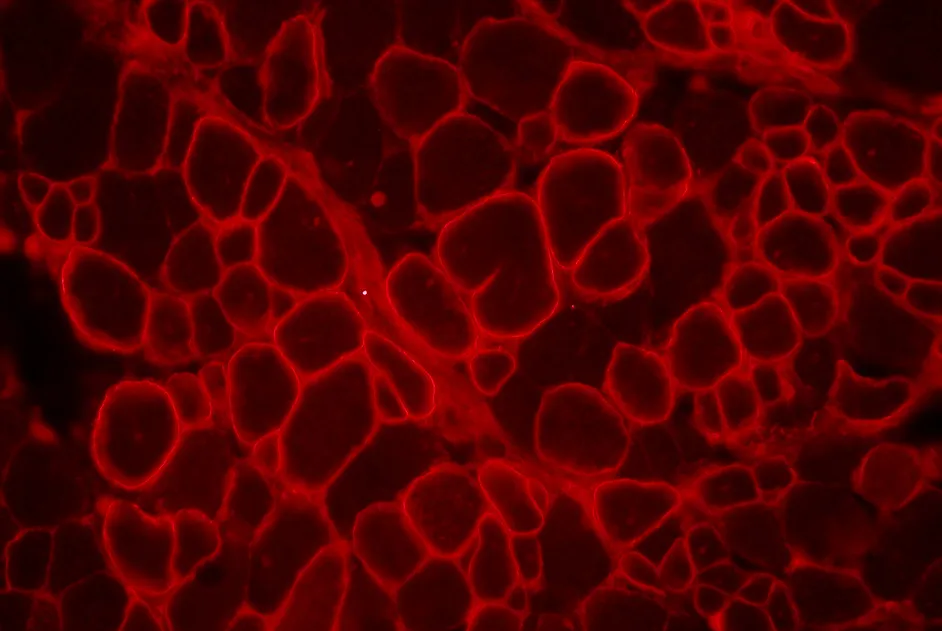

A compter de l’été 2013, les malades affectés par un déficit en lipoprotéine lipase (LPL) disposeront d’un médicament de thérapie génique préventif contre les attaques pancréatiques graves et régulières.